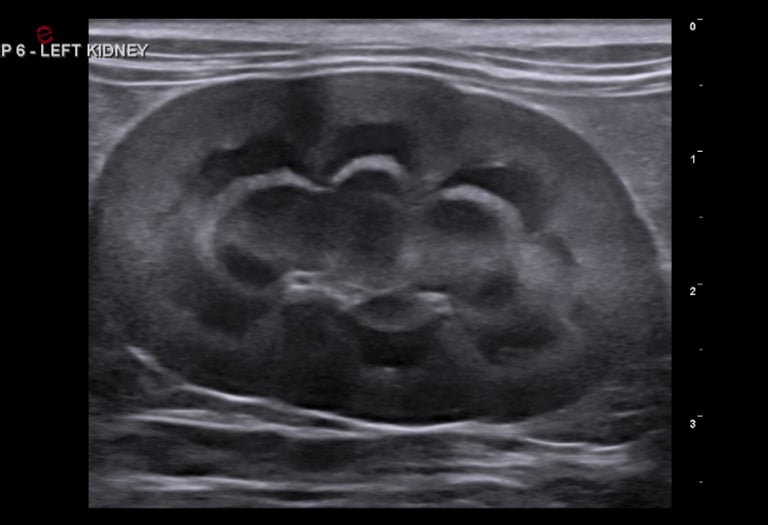

abdominal ultrasound

Complete abdominal ultrasound captures detailed videos and images of internal organs to aid in the diagnosis of various conditions and help guide treatment decisions.

Organs interrogated include liver, gallbladder, pancreas, adrenal glands, kidneys, bladder, spleen, colon, stomach, small intestines, lymph nodes, vessels, +/- reproductive organs.